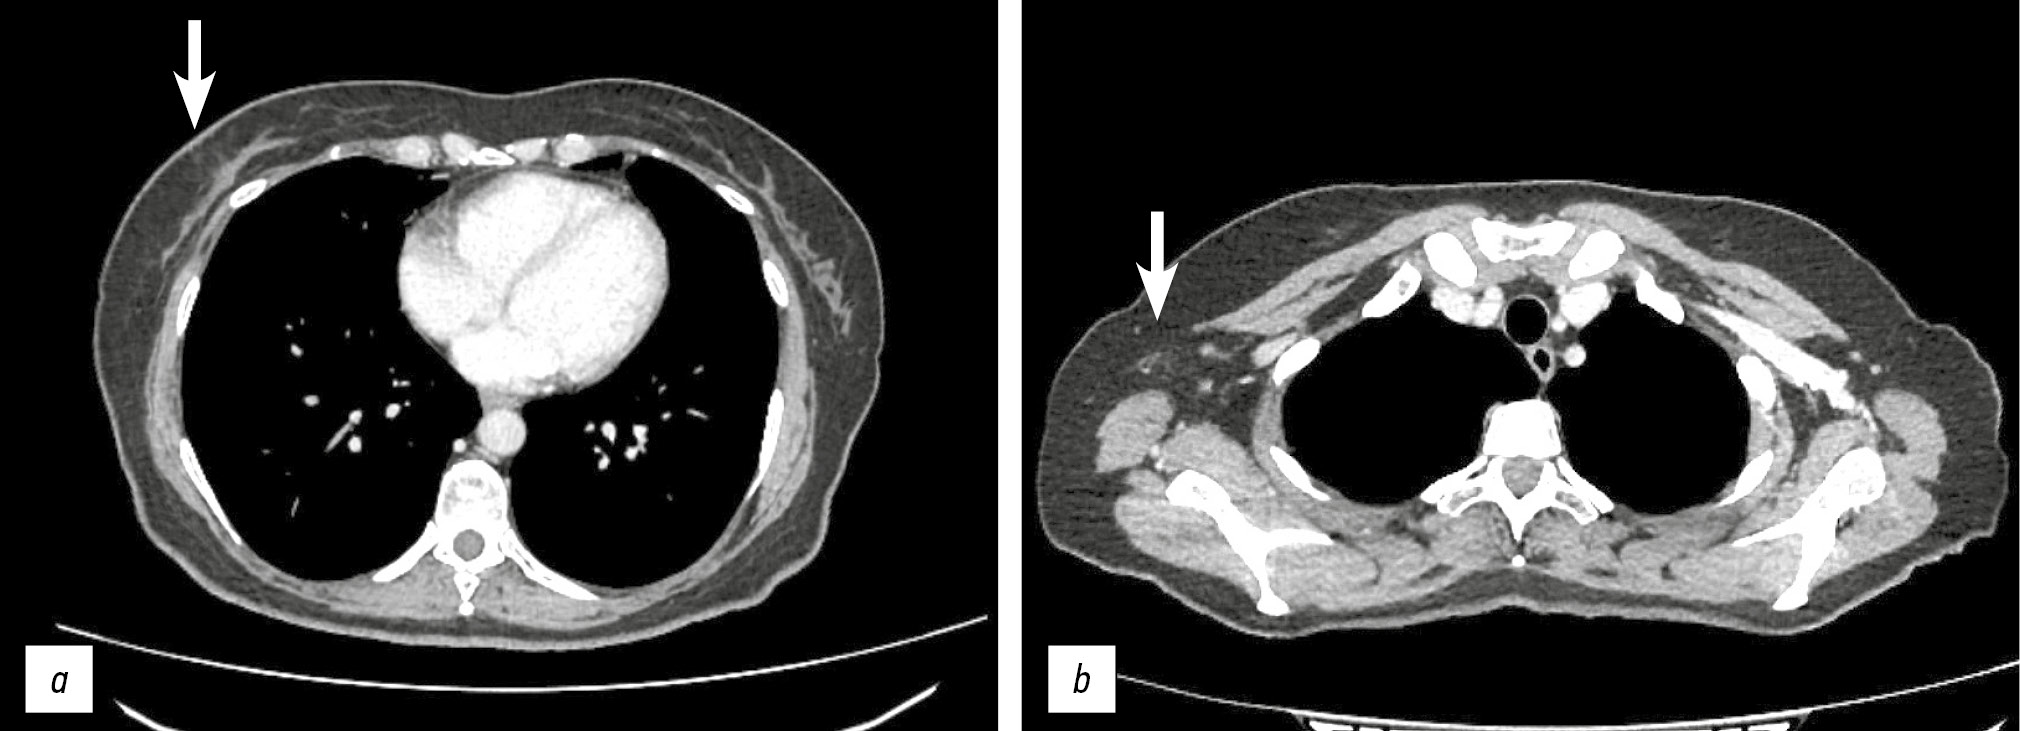

On April 11, 2023, chest multislice CT was performed. No infiltrative or focal lesions were in the lung fields. Mediastinal lymph nodes were not enlarged. In the lower outer quadrant of the right breast, the previously detected mass was not visualized; on the right, both previously enlarged axillary lymph nodes measured 0 mm along the short axis (Fig. 2a, b). SoD was 0 mm. The response was 100%, with complete regression of the breast tumor, supraclavicular and axillary lymph nodes.

Fig. 2. Computed tomography of the chest from 11.04.2023. In the lower-outer quadrant of the right breast, the previously identified formation is not defined (a). Enlarged lymph nodes in the axillary region on the right are not identified (b).